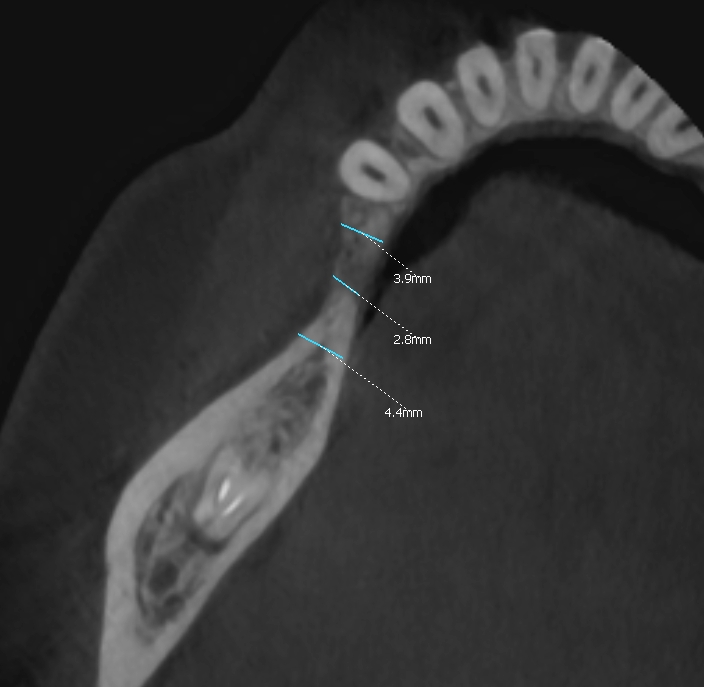

Ryc. 2. Szerokość wyrostka. Ryc.  3. Deficyt objętościowy masy kostnej i zanik blaszki przedsionkowe.

Po okresie 6 miesięcy wykazano prawidłową resorpcję cementu i regenerację wyrostka poprzez odtworzenie kości żywiciela (pacjenta) do szerokości około 8 mm (ryc.13).

Regenerację blaszki przedsionkowej potwierdzono także klinicznie po odwarstwieniu płata podczas zabiegu planowej implantacji. Zmierzono szerokość wyrostka na poziomie 7-8 mm (ryc.14). Po wyrównaniu płaszczyzny wyrostka (ryc. 15) wykonano łoża dla implantów śrubowych w okolicy 45 (dł. 10 mm, śr. 3.7 mm) i 46/47 (dł. 10 mm, śr. 4.1 mm) (ryc.16), które wprowadzono w kość z momentem obrotowym około 25 Ncm. Ranę zaopatrzono szwami (PTFE – politetrafluoroetylen 4-0, igła odwrotnie tnąca, profil 3/8 koła długość 16 mm) (ryc.17).